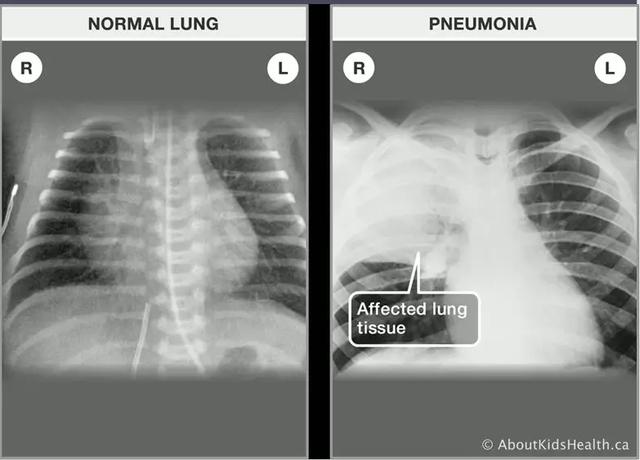

The Coronavirus can cause pneumonia.

冠状病毒能引起肺炎。

Pneumonia is swelling (inflammation) of the tissue in one or both lungs.

肺炎是肺部组织肿大。

At the end of the breathing tubes in your lungs are clusters of tiny air sacs. If you have pneumonia, these tiny sacs become inflamed and fill up with fluid.

肺部的呼吸末端是细小的空气囊,肺炎导致空气囊发炎并充满液体。